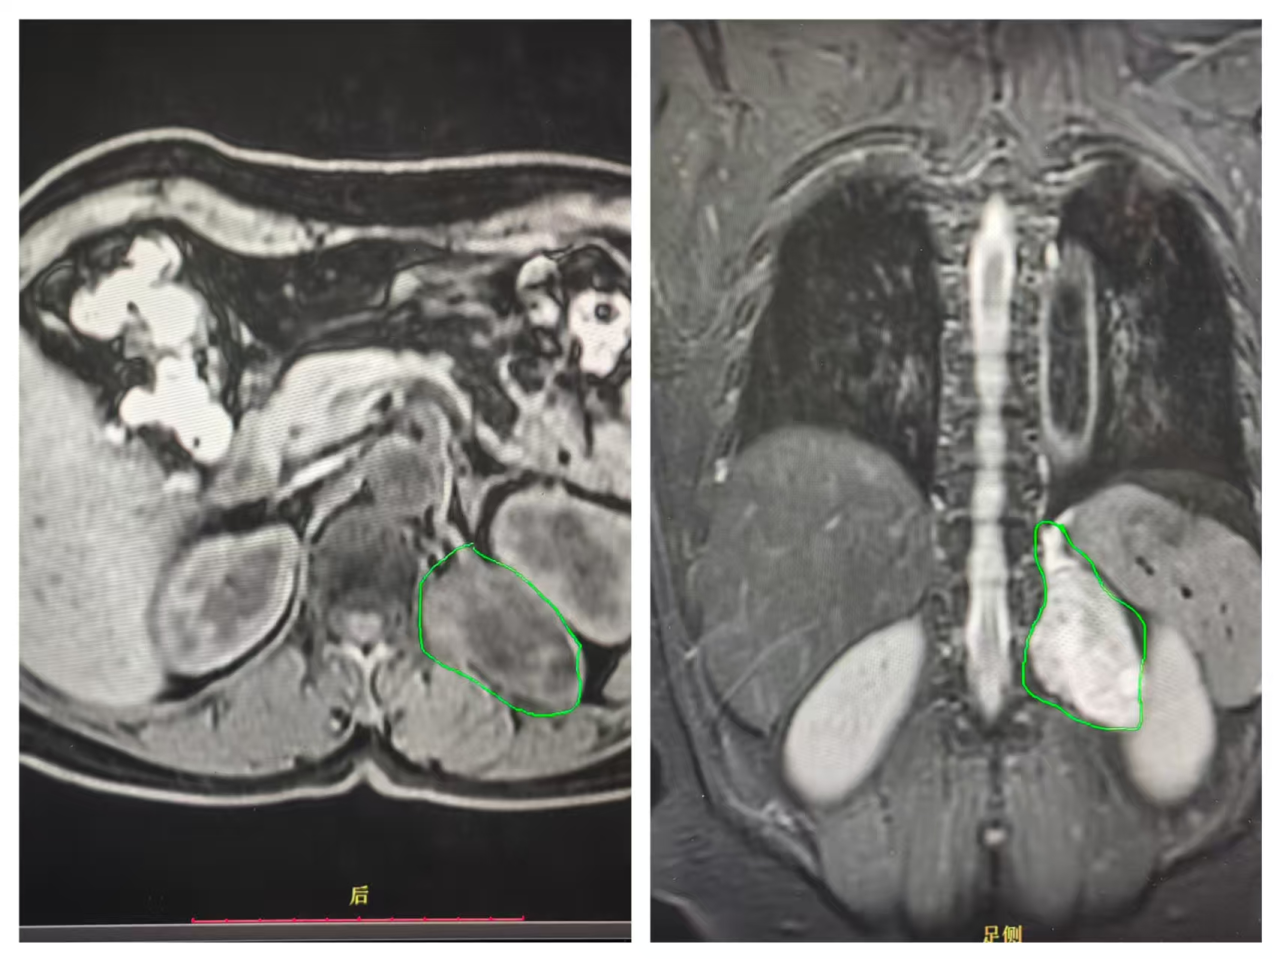

一、胸部肿瘤诊疗:突破技术瓶颈,提升救治能力 高龄食管癌手术自主完成 面对高龄患者手术高风险挑战,科室独立完成82岁食管癌根治术,全程自主把控手术操作与围术期管理,患者术后恢复良好。此次手术标志着我院胸部外科麻醉、医疗及护理体系日趋成熟,为食管肿瘤患者提供了新的治疗选择。 局部晚期肺癌手术稳步推进 针对局部晚期肺癌患者,科室凭借精准的手术规划与精细化围术期管理,成功完成多例手术,为患者争取了治疗时机与生存机会。 转化治疗策略改善晚期肺癌预后 对于初始不可手术的晚期肺癌患者,对接前沿技术,联合肿瘤科开展化疗联合免疫治疗的“转化治疗”策略,成功缩小肿瘤体积并实现降期,最终通过外科手术完整切除病灶。该案例体现了我院MDT团队协作优势,为晚期肺癌患者开辟“带瘤生存”向“无瘤生存”转化的路径。 后纵隔肿瘤诊疗能力提升 先后完成“后纵隔巨大肿瘤综合治疗”“后纵隔复杂肿瘤外科切除”等手术,推动肿瘤综合治疗水平稳步提升。 二、甲状腺疾病诊疗:微创与美容结合,优化治疗体验 腔镜甲状腺手术实现“无痕化”进展 引进“腋下美容切口”“胸乳入路腔镜手术”等技术治疗甲状腺肿瘤,在保证疗效的同时减少手术创伤,兼顾患者美观需求,标志着科室在微创技术道路上迈出坚实步伐。 复杂胸腺肿瘤微创治疗落地 成功开展“剑突下切口微创胸腺肿瘤切除术”,通过微小切口完成深部肿瘤精准切除,术后患者疼痛轻、恢复快,为胸腺肿瘤患者提供新的治疗选择。 三、乳腺疾病诊疗:精准与人文并重,守护女性健康 乳腺癌一体化诊疗模式逐步完善 科室推进早期乳腺癌保乳手术开展,对晚期乳腺癌实施新辅助治疗后再手术,建立“筛查-诊断-治疗-康复”一体化诊疗模式,让患者在家门口就能享受便捷医疗服务。 四、血管与功能性疾病:微创技术解难题,提升患者满意度 功能性疾病微创治疗优化 在腋臭、手汗症等功能性疾病的微创治疗中,科室采用mini切口无痕手术、胸腔镜下交感神经切断等技术,术后效果明显且疤痕隐蔽;静脉输液港植入为肿瘤患者建立“生命通道”。 下肢静脉曲张治疗技术升级 推广“外科微创下肢静脉曲张治疗+硬化剂注射”等新技术,兼具美容、高效优势,对晚期合并溃疡患者效果明显。 五、多学科协作(MDT):强强联合,攻克复杂病例 高危复杂病例协作救治成功 面对颈部巨大肿物压迫导致顽固性高血压、心脏功能恶化的高危患者,科室联合心血管内科、麻醉科组建MDT团队,术前植入临时起搏器保障心脏安全,术中全程严密监护,最终精准切除肿瘤。该案例体现了我院在颈部神经血管危险区多学科协作的能力。 肺结节MDT诊疗方案落地 健全肺结节多学科诊疗(MDT)团队,优化定向追踪随访机制。对中高位风险患者,利用设备和技术优势进行结节特殊“靶扫描”,提高诊断准确率,为后续精准诊疗奠定基础。 回望2025,胸甲状腺乳腺血管外科在多个重点领域的进展,让患者切实感受到“大病不出县”的便利。未来,科室将继续秉持“以患者为中心”的理念,深耕技术创新,强化团队协作,在守护生命的征程上勇毅前行,为区域医疗发展贡献力量。